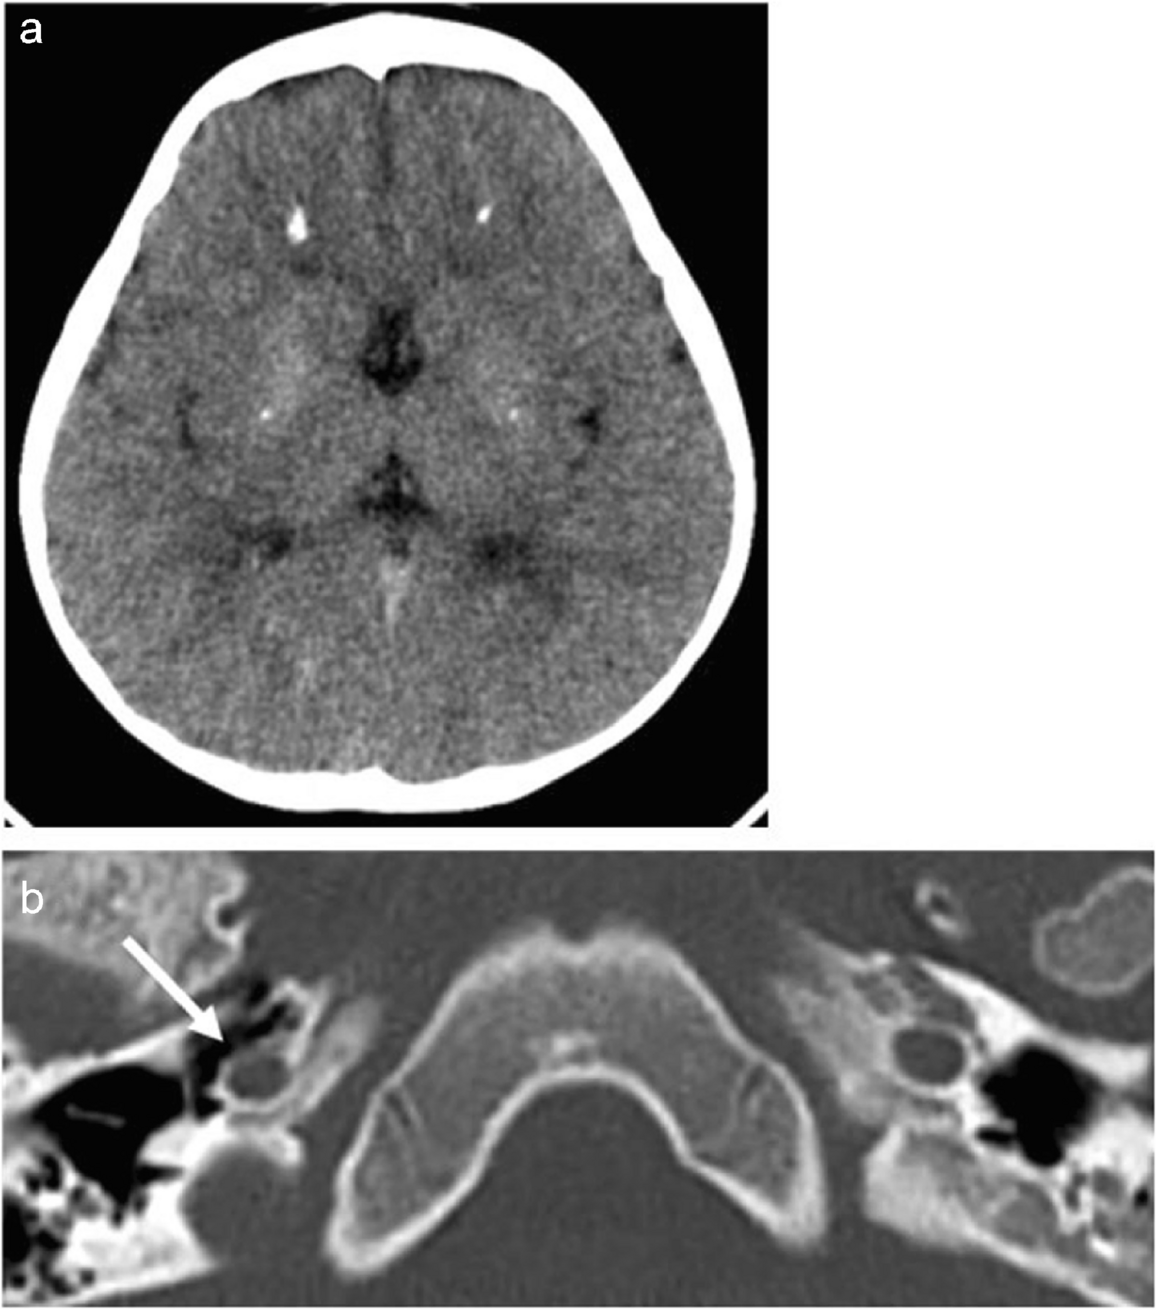

Fig. 2

Computed tomography of the brain in a 3-year-old girl with Aicardi-Goutières syndrome. a Symmetrical calcifications in the periventricular frontal white matter and lenticulate nuclei. b Mild hypoplasia of the right carotid canal in the petrous bone (arrow)

The girl underwent successive brain imaging. At 15 months of age, the spinal-cord magnetic resonance imaging (MRI) findings were normal, and brain MRI revealed delayed myelination and T2 hypersignals in the periventricular white matter (Fig. 1). At 2 years and 6 months of age, brain MRI additionally revealed symmetrical clusters of hyposignals on susceptibility-weighted images, suggesting calcifications in the periventricular frontal white matter. Therefore, brain computed tomography (CT) was performed (at the age of 3 years and 2 months), and the findings confirmed the scattered calcifications in the periventricular frontal white matter and in the lenticulate nuclei (Fig. 2). These results suggested Aicardi-Goutières syndrome or pseudo-TORCH syndrome; however, TORCH infections were excluded. Trio-based whole-genome sequencing revealed a homozygous p.Arg290 Cys variant in the SAMHD1 gene (Chr20(hg38):g.36917034G>A;NM_015474.4:c.868 C>T). Each parent was heterozygous for the variant. This variant has previously been reported in a patient with interferonopathy and was considered pathogenic (class 5 according to the American College of Medical Genetics and Genomics) [3]. This finding led to the performance of another brain MRI with 3D time-of-flight (TOF) angiography at 4 years and 3 months of age, which revealed severe stenosis of the left middle cerebral artery origin, with a dilated collateral arterial network (moyamoya syndrome); long stenosis of the right posterior cerebral artery; and mild narrowing of the right internal carotid artery (Fig. 3). No ischaemic lesions were detected on diffusion-weighted, T1-weighted, or T2-weighted images. Even retrospectively, no obvious intracranial arterial stenosis was visible on conventional MRI sequences. Retrospectively, brain CT revealed mild hypoplasia of the right carotid canal at the level of the petrous bone (Fig. 2). The narrowing of the right internal carotid artery was considered a congenital anomaly (i.e., hypoplasia) rather than an acquired process (i.e., stenosis).